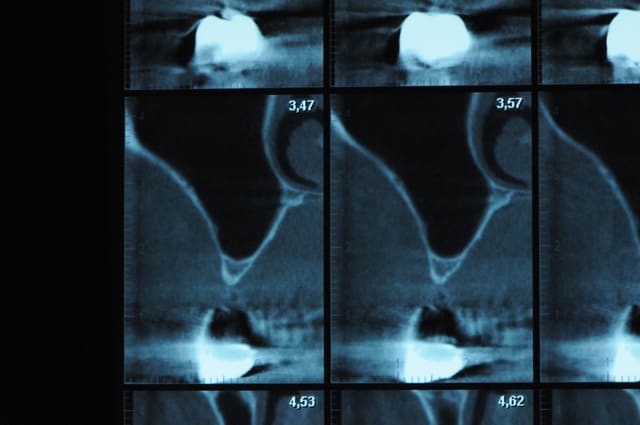

scanner...

aspect des crêtes et début du sinus lift.

l'os était tellement fin qu'il n'y avait presque pas besoin de la piezo.